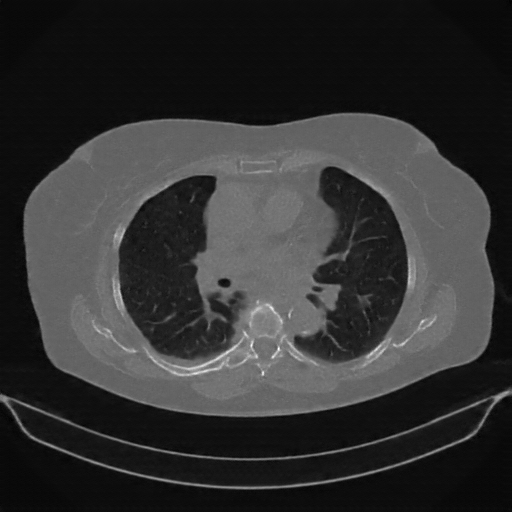

Targeted Slice 70 - Lung Window Analysis (Generated vs Real Venous)

0.676

Lung SSIM

119.5

Lung RMSE

52.1

Lung MAE

Average Lung Window Metrics Across All Slices (58 slices) - Generated vs Real Venous

0.690

Lung SSIM (Avg)

110.0

Lung RMSE (Avg)

49.3

Lung MAE (Avg)

Generated VENOUS CT scan (A→B translation)

No window - Raw intensity values

Mediastinum window (WL 40, WW 400 β†’ Low βˆ’160, High +240)